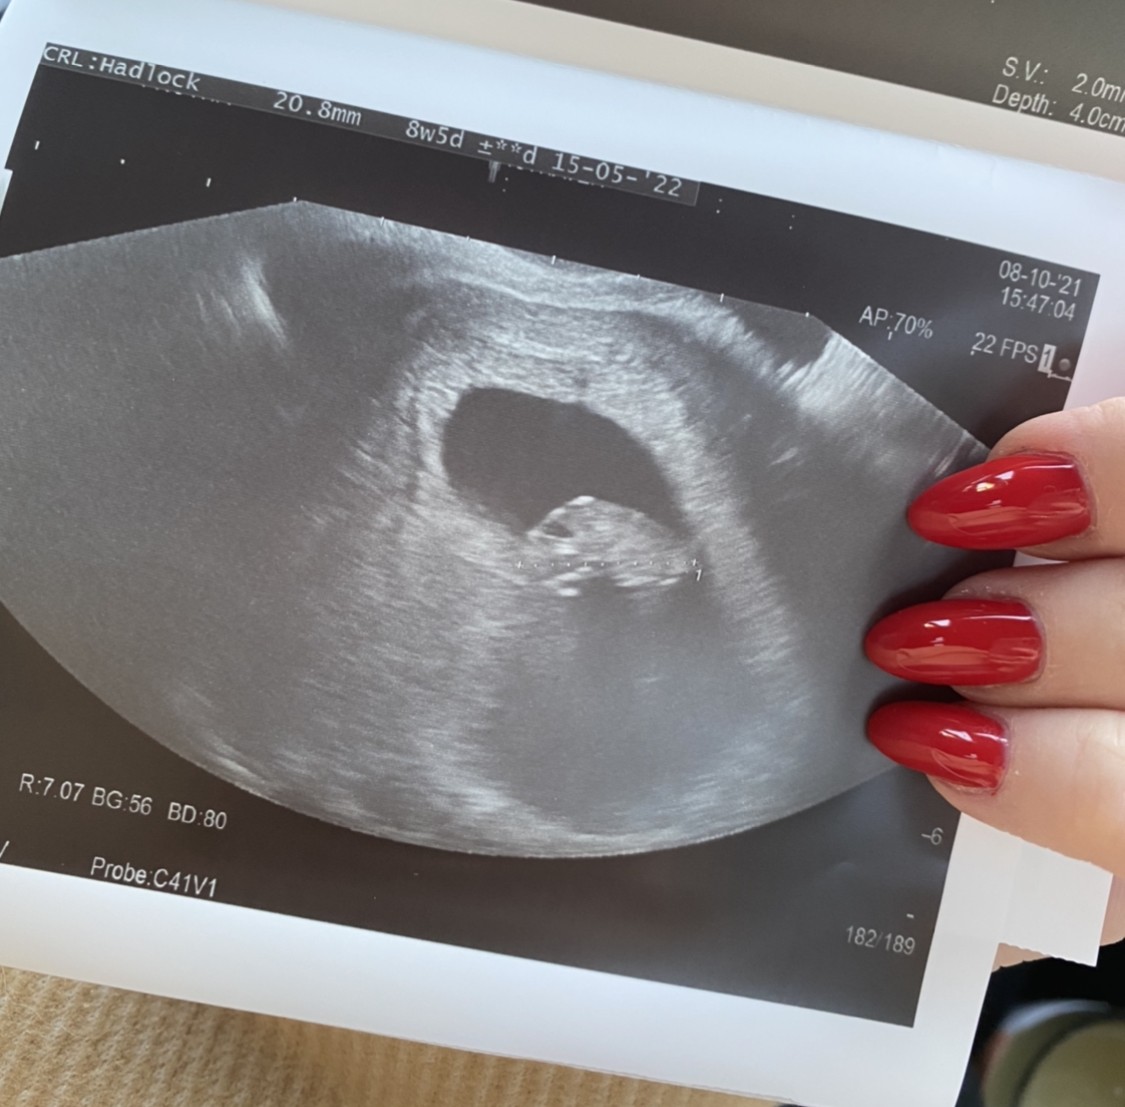

tak, serduszko widzialam w 6t1d, a jesli chodzi o usg z 8 tygodnia to tak wygladaloA byłaś może na USG w 8 tygodniu ?